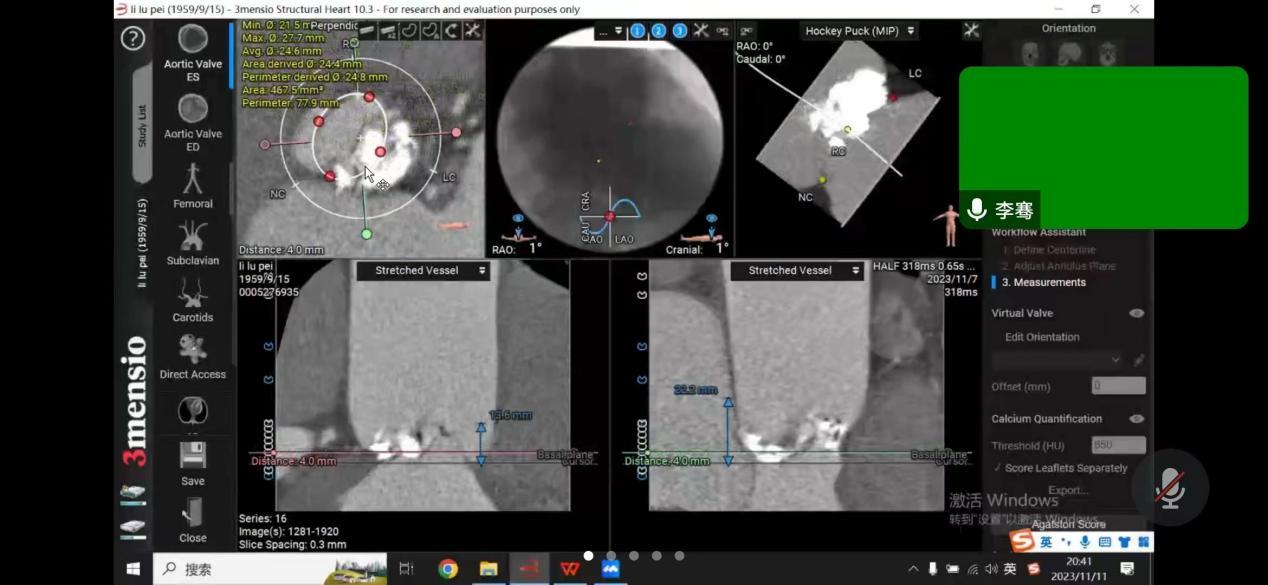

患者是一位64岁男性,反复胸闷憋气多年,未规律就诊,此次因慢性心力衰竭急性加重,心源性休克,多器官衰竭,由基层医院转至樱花动漫 。经过医院ICU团队抢救治疗后,患者病情转危为安;随后为患者完善超声心动图检查,提示主动脉瓣病变,TYPE-0型二叶式主动脉瓣,主动脉瓣钙化、重度狭窄并轻度反流,二尖瓣中度反流,三尖瓣中度反流,主动脉瓣前向血流速度4.9m/s,峰值压差95mmHg,行主动脉瓣换瓣治疗指针。由于能够反应患者左心室收缩功能的射血分数(EF值)仅占23%,心功能差,基础情况差,升主动脉瘤样扩张,收缩期心室增大明显,左室内径达60mm,心尖薄,不能承受开胸换瓣手术。心内科介入下行TAVR治疗的难度在于该病人为一例典型Type0型二叶式主动脉瓣重度狭窄患者,人工瓣膜定位及锚定难度大,患者瓣叶重度钙化,存在人工瓣膜形变、瓣环撕裂、根部损伤以及术后出现瓣周漏等风险。楚天舒主任团队对患者病情进行整体评估后,将患者情况汇报医院医务处,医务处组织心血管内科、麻醉手术科、心脏血管外科、重症医学科等进行术前多学科联合会诊,结合患者实际情况,多次讨论,为患者制定最佳手术方案,最后决定给该患者行介入导管微创瓣膜手术(TAVR)。多位专家一起制定了详尽的诊疗及手术方案,并准备了多套的应急预案。

11月12日下午,楚天舒主任团队成功为患者进行了TAVR换瓣治疗,手术中通过导管测量得到植入前心室主动脉压力差大于90mmHg,提示主动脉瓣狭窄已严重阻碍心脏正常泵血工作。人工瓣膜成功植入后,可见人工瓣膜瓣叶开阖自如,心脏对外泵血压力明显减轻,导管测得压力阶差降至10mmHg以下,血流动力学即刻得到改善。这提示着患者的主动脉瓣狭窄情况,已较前大为缓解,手术圆满成功。术后患者生命体征平稳,带气管插管安全返回ICU特护。一天后,患者被转回心血管内科二病区继续治疗。在心血管内科二病区全体医务人员的精心治疗与护理下,患者于17日顺利出院。